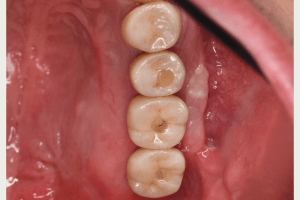

インプラント治療の症例4

口腔内写真

- Befor

- After

| 年齢 | 50代・男性 |

| 主訴 | 部位:左下6番7番 主訴:左下奥歯腫れて痛い。 |

| 治療内容 | 左下6番抜歯、左下6番7番骨造成、インプラント埋入 |

| 治療費 | 合計:1,232,000円 ・内訳 診断料:55,000円 サージカルガイド2本:66,000円 GBR:110,000円×2本 埋入料:165,000円×2本 静脈内鎮静麻酔:77,000円 2次OPE:22,000円×2本 仮歯:55,000円×2本 上部構造(フルジルコニア):165,000円×2本 (2023年1月現在) |

| 治療期間 | 約8ヶ月 |

| 治療方針 | 元々支台歯に負荷がかかりやすいとされている延長ブリッジを抜歯し、1本単体でしっかりかめるようにインプラントを2本埋入した。骨吸収も進んでいたため、※GBR法で骨造成を同時に行った。 治療と並行して、全顎的な歯周病治療も行い、今後は歯周病が進行しないよう、こまめにメンテナンスに通っていただく。 |

| 特記事項 | ※1 GBR・・・骨再生誘導法。骨の高さや厚みを人工骨や人工膜などを使用し再生する方法 |

| 担当者所見 | 6番は歯根分割された被せ物が7番の欠損部との延長ブリッジとされており、強い咬合と歯周病も相まって負荷がかかり動揺し、歯として機能しなくなったため、抜歯となった。 |